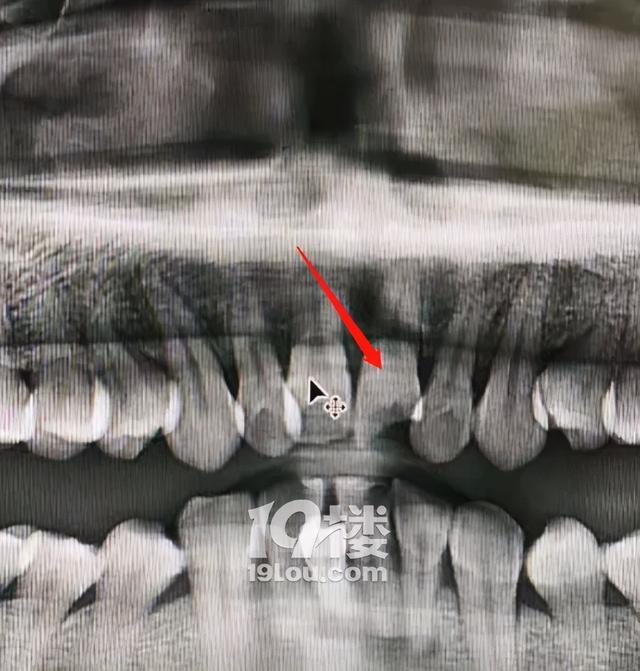

虽然此男子上嘴唇撕裂缝了3针,上门牙也被撞掉半颗,但够不上最低的第十级伤残标准,根据2017年1月1日起施行的《人体损伤致残程度分级》标准规定十级伤残标准为“唇缺损或者畸形,致露齿;牙齿缺失或者折断7枚以上;牙槽骨部分缺损,合并牙齿缺失或者折断4枚以上”。